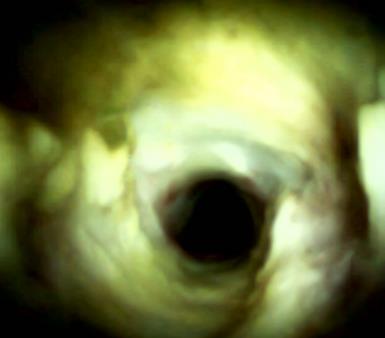

• 不同入路脊柱内镜手术治疗L4/5节段脱垂型腰椎间盘突出症的疗效比较

摘要:目的 观察经椎间孔入路内镜下腰椎间盘切除术(TELD)和经椎板间入路内镜下腰椎间盘摘除术(IELD)治疗L4/5节段脱垂型腰椎间盘突出症(LDH)的临床疗效。方法 回顾性分析2020年11月-2022年11月该院采用脊柱内镜手术治疗的75例L4/5节段脱垂型LDH患者的临床资料。根据手术入路的不同,将患者分为TELD组(53例)和IELD组(22例)。比较两组患者的手术情况和术后疗效。结果 与TELD组比较,IELD组的手术时间明显缩短,术中透视次数明显减少,差异均有统计学意义(P < 0.05);两组患者住院时间和并发症发生率比较,差异均无统计学意义(P > 0.05)。所有患者术后均获得12~19个月的随访。两组患者末次随访时的视觉模拟评分法(VAS)评分和Oswestry功能障碍指数(ODI)明显低于术前,且IELD组明显低于TELD组,差异均有统计学意义(P < 0.05)。按照突出物和神经根的不同位置进一步分析,两组肩上型患者(TELD组10例,IELD组6例)末次随访时的VAS评分和ODI明显低于术前,且IELD组末次随访时的VAS评分明显低于TELD组,差异均有统计学意义(P < 0.05);两组腋下型患者(TELD组8例,IELD组16例)末次随访时的VAS评分和ODI明显低于术前,且IELD组明显低于TELD组,差异均有统计学意义(P < 0.05);35例肩前型患者经TELD术后,末次随访时的VAS评分和ODI明显低于术前,差异有统计学意义(P < 0.05)。按照突出物的不同Lee分区进一步分析,两组Lee Ⅲ区患者(TELD组44例,IELD组10例)末次随访时的VAS评分和ODI明显低于术前,且IELD组的ODI明显低于TELD组,差异均有统计学意义(P < 0.05);两组Lee Ⅳ区患者(TELD组9例,IELD组12例)末次随访时的VAS评分和ODI明显低于术前,且IELD组明显低于TELD组,差异均有统计学意义(P < 0.05)。结论 采用TELD和IELD治疗L4/5节段脱垂型LDH,均可获得较满意的减压效果,但IELD的手术时间相对较短,X线透视次数较少,且对肩上型、腋下型、Lee Ⅲ区和Lee Ⅳ区的减压效果更有优势。